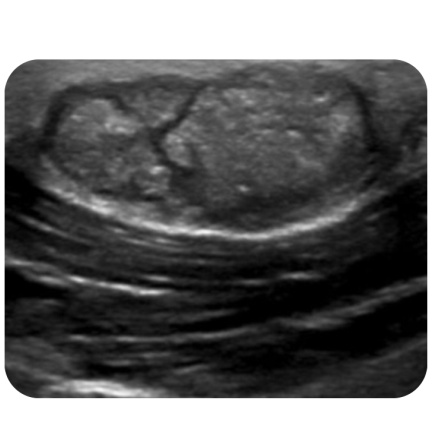

1.医生通过触诊及B超检查进行初步诊断。B超检查主要了解肿瘤的大小、性质、位置及血流情况。(*钙化上皮瘤有特征性表现:内部可见钙化灶;图左-表皮囊肿申宝配资,图右-钙化上皮瘤 )

图左-表皮囊肿

图右-钙化上皮瘤